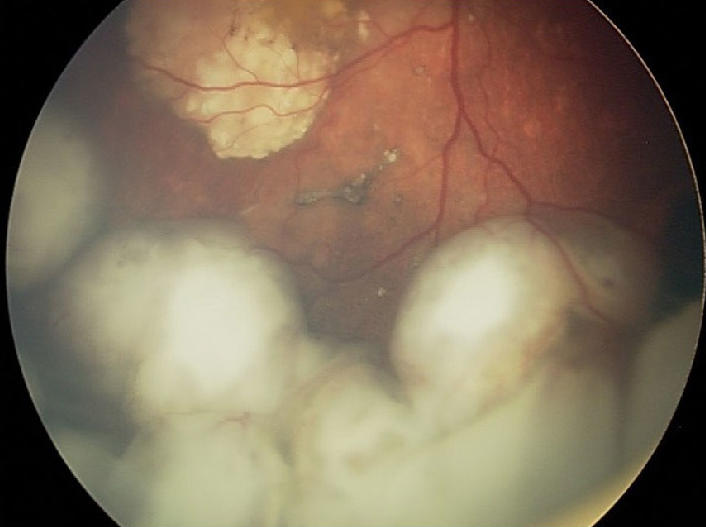

As its name implies, retinoblastoma develops in the retina, in the back of the eye. In the United States, only a few hundred children, mostly kids younger than 2 years old, are diagnosed with this cancer every year. About 40% of these cancers are due to an inherited genetic mutation in a gene called RB1. In most patients with the inherited form of retinoblastoma, the cancer affects both eyes.

For example, when the researchers injected hydrogel-encapsulated GD2/IL-15 CAR T cells into tumors in the mice, they were completely eliminated in all of the mice and did not return for the duration of the study. Additional experiments found that the CAR T cells remained around the tumor site, which is important to help prevent the tumor from recurring.

In addition, the therapy “also improved structural recovery of the retina” in the mice, they reported. Additional analyses showed that untreated mice had significantly impaired retinal function, whereas mice that received the hydrogel-packaged treatment appeared to have good retinal function.

Drs. Nellan and Fry called the results from the mouse studies “promising,” particularly because of the limited damage to the retina and the finding “that this treatment results in improved [retinal] function.”

Dr. Gonzalez agreed that hydrogel-packaged CAR T cells are promising and should continue to be developed. The treatment’s impact on the retina will need further scrutiny, he added, because the mouse model used in the study doesn’t replicate the retinal damage that is often present in children by the time they are diagnosed with this cancer. “At that point, they often already have some dysfunction of the retina,” he said.